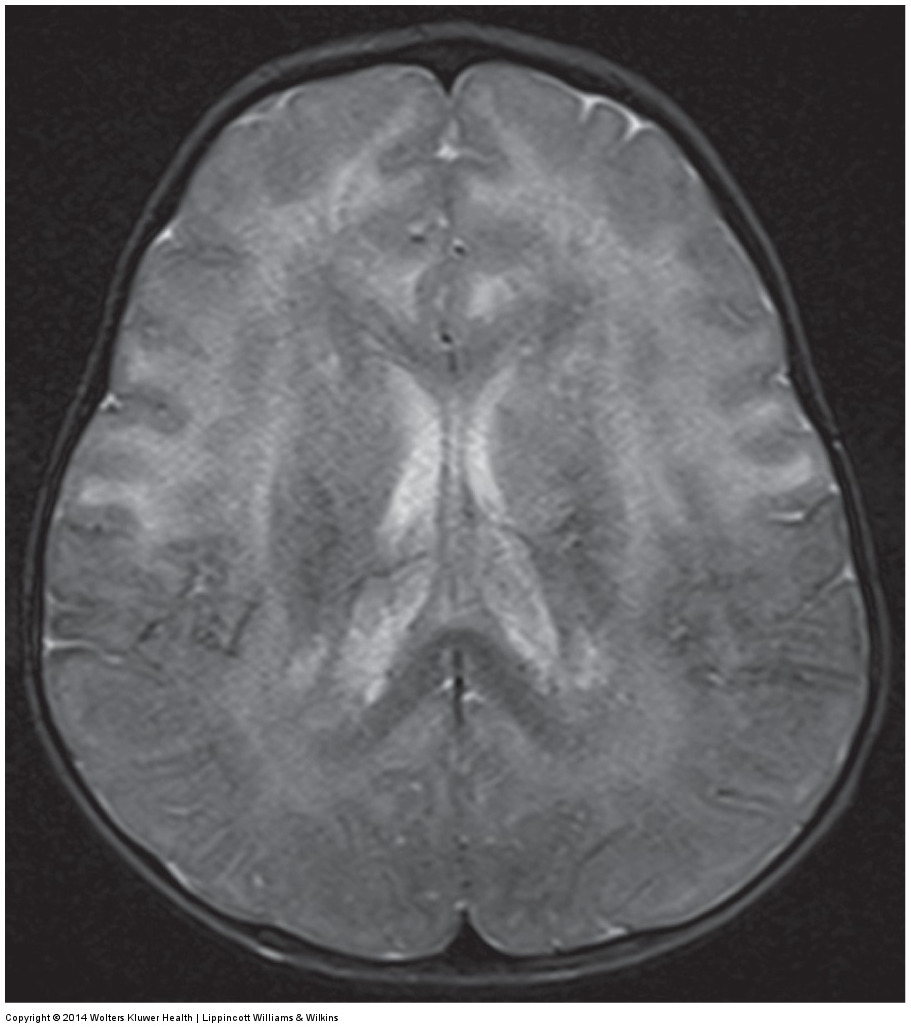

MRI shows asymmetric parietal cortical atrophy, sometimes with associated hyperintensity of the white matter on T2W images.

Axial FLAIR image shows striking asymmetric cortical parietal atrophy in a patient with CBD